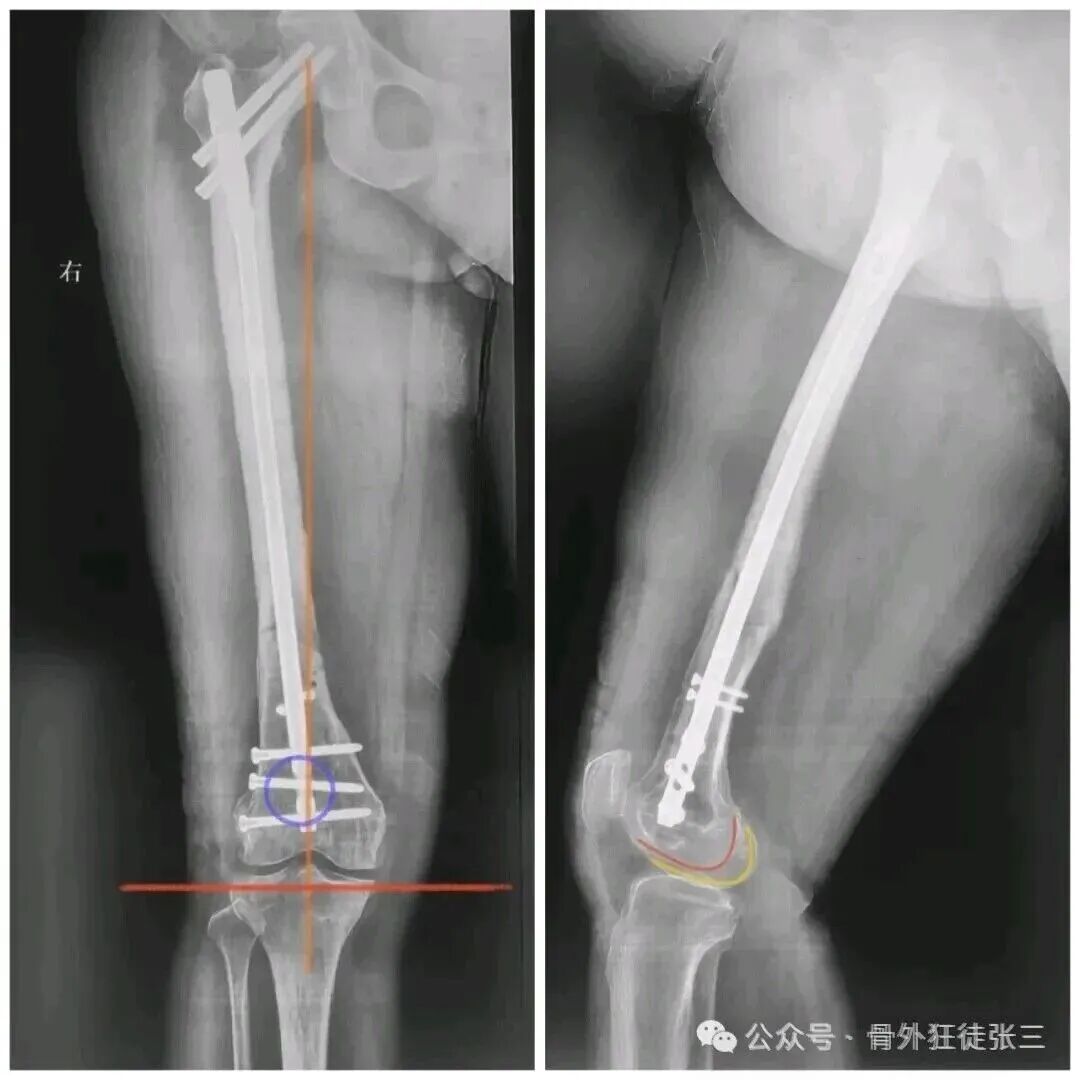

我们给予翻修

1,顺行髓内钉,头颈模式

2,全长保护,

3,最粗,够长

这样全长保护

转子下,股骨颈或者股骨远端再骨折的概率

是不是非常小

几乎不会再出现?

所以还是坚持我们的观念

股骨干骨折

能髓内钉,不钢板

能顺行,不逆行

能闭合,不切开

髓内钉,要顶天立地

够粗,够长,够坚强